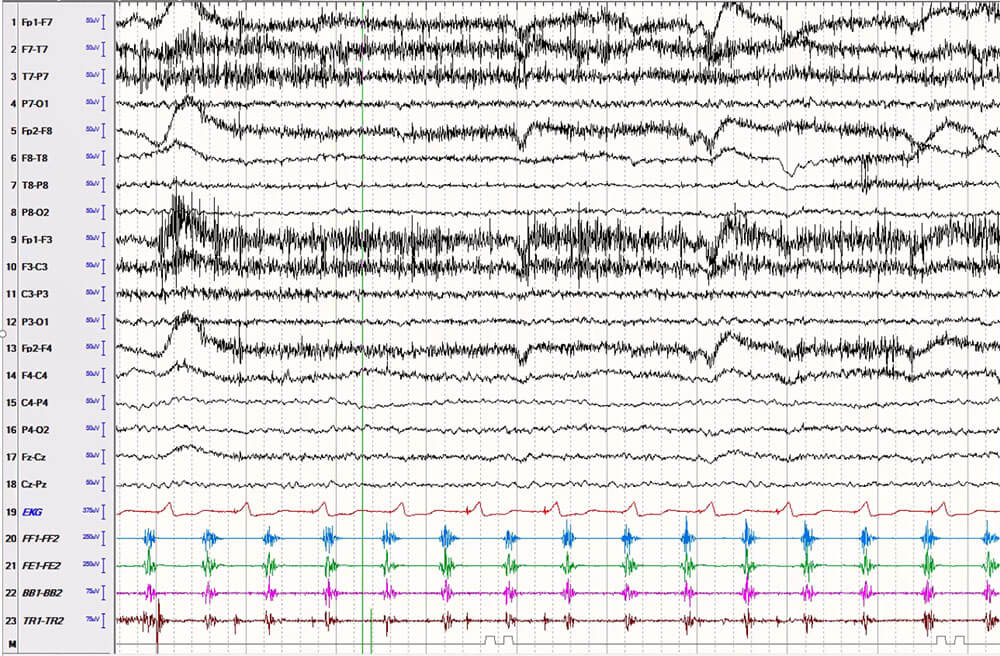

Dr. Fotedar and his colleagues retrospectively reviewed video-EEG recordings of 39 patients admitted to University Hospitals between 2016 and 2022 with clonic seizures to analyze the semiology and ictal EEG findings.

“As a Level 4 epilepsy center treating complex nonlesional epilepsy patients, we rely on seizure semiology to identify the epileptogenic zone as an essential component of presurgical planning,” he says. “Because we had both EEG and video recording of these patients’ seizures, we were able to analyze the simultaneous data and make correlations about where the clonic seizure originated and how it affected the body.”

The team also utilized surface electromyography processing (EMG) to gather additional recordings for 17 patients in the study. “We developed a protocol within the UH Epilepsy Center for how to place these electrodes to map muscle activation patterns in clonic seizures,” Dr. Fotedar says. “As far as I am aware, our study is the first and largest to report the surface EMG characteristics of this prevalent type of seizure.”